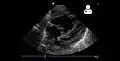

مخطط صدى القلب

يتم عمل تحليل ميتا عن طريق صدى الصوت الناتج عن تأثير دوبلر للتنبؤ بالقسطرة، هذا يعطي حساسية بنسبة 88% وفعالية بنسبة 56%.[9]

- مخطط صدى القلب.